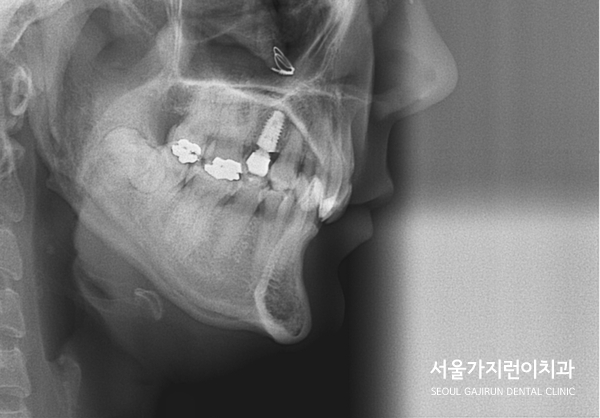

문제는 상악 우측 제1대구치에 임플란트를 식립한 환자라는 점입니다.

임플란트는 교정력이 있어도 이동하지 않으며 이 부분에 힘이 가해질 경우

임플란트의 파손으로 이어질 수 있어 상당한 주의가 필요한데요.

임플란트의 존재와 임플란트 주변의 치아 이동에 제한이 있기 때문에

꼼꼼한 교정플랜이 뒷받침되어야 했습니다.